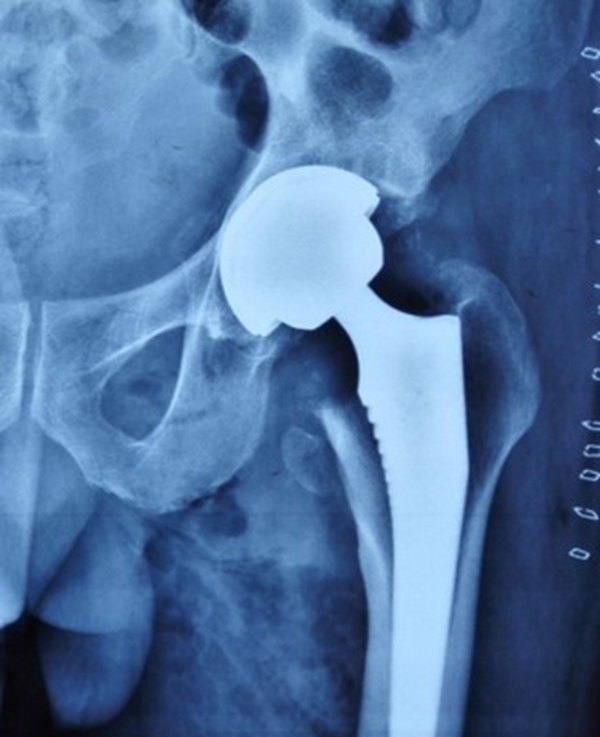

全髋关节置换术具有优异的疼痛缓解、稳定可靠的固定及良好的功能恢复和长期随访结果等优点,常用于治疗各种晚期髋关节疾病。在全髋关节置换中,畸形常发生在股骨侧,非常难处理,是髋关节置换中难题之一。

2、假体选择

①保留畸形:表面髋置换、短柄假体。

②让骨骼适应假体:股骨截骨。

③让假体适应畸形:组配式假体

④hybrid、水泥柄。